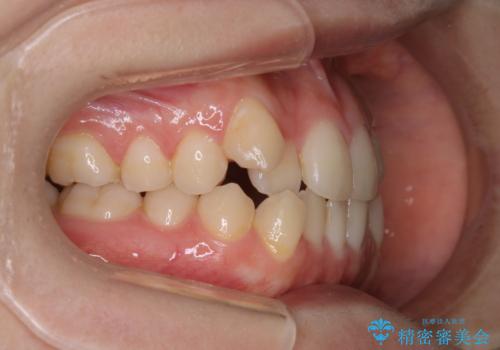

マイクロインプラントを使用して抜歯を回避!八重歯の非抜歯インビザライン治療

- 非抜歯、インビザライン治療希望の患者様です。

右の犬歯が八重歯になっており、通常であれば抜歯を選択する可能性が高くなりますが、

マイクロインプラントと呼ばれる骨に打ち込むネジを使用し、非抜歯での治療計画を立てました。